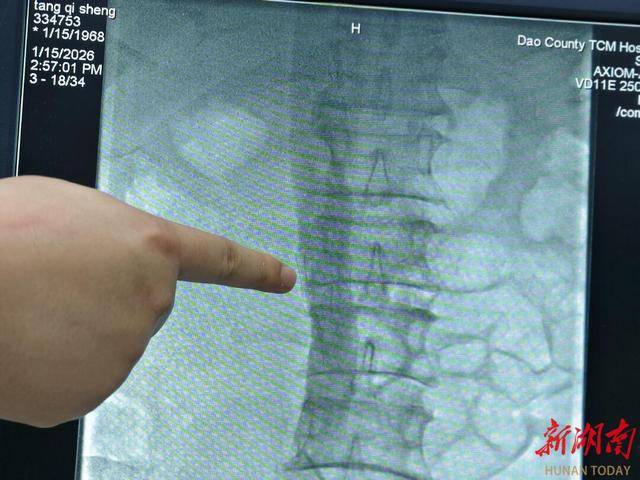

1月15日下午,外二科黄竹旺医师在长沙市第一医院贺超贵老师的指导下,顺利为两位患者实施经皮静脉内滤网置入术治疗,手术伤口微创,患者术后无需卧床制动,行动与平常无异,次日下肢水肿情况明显缓解。患者及家属对该手术治疗效果非常满意。

他强调,经皮静脉内滤网置入术通常在局部麻醉下进行,经股静脉或颈静脉穿刺,在X线或超声引导下完成,手术时间一般短于30分钟,但是否需要放置滤器应由血管外科、介入科、血液科等医生共同评估,多学科决策。术后还需积极处理原发病,一旦抗凝禁忌消除,应尽快重启抗凝治疗。